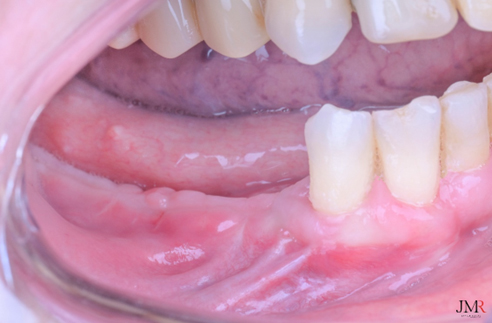

Cicatrización de la zona a los 40 días.